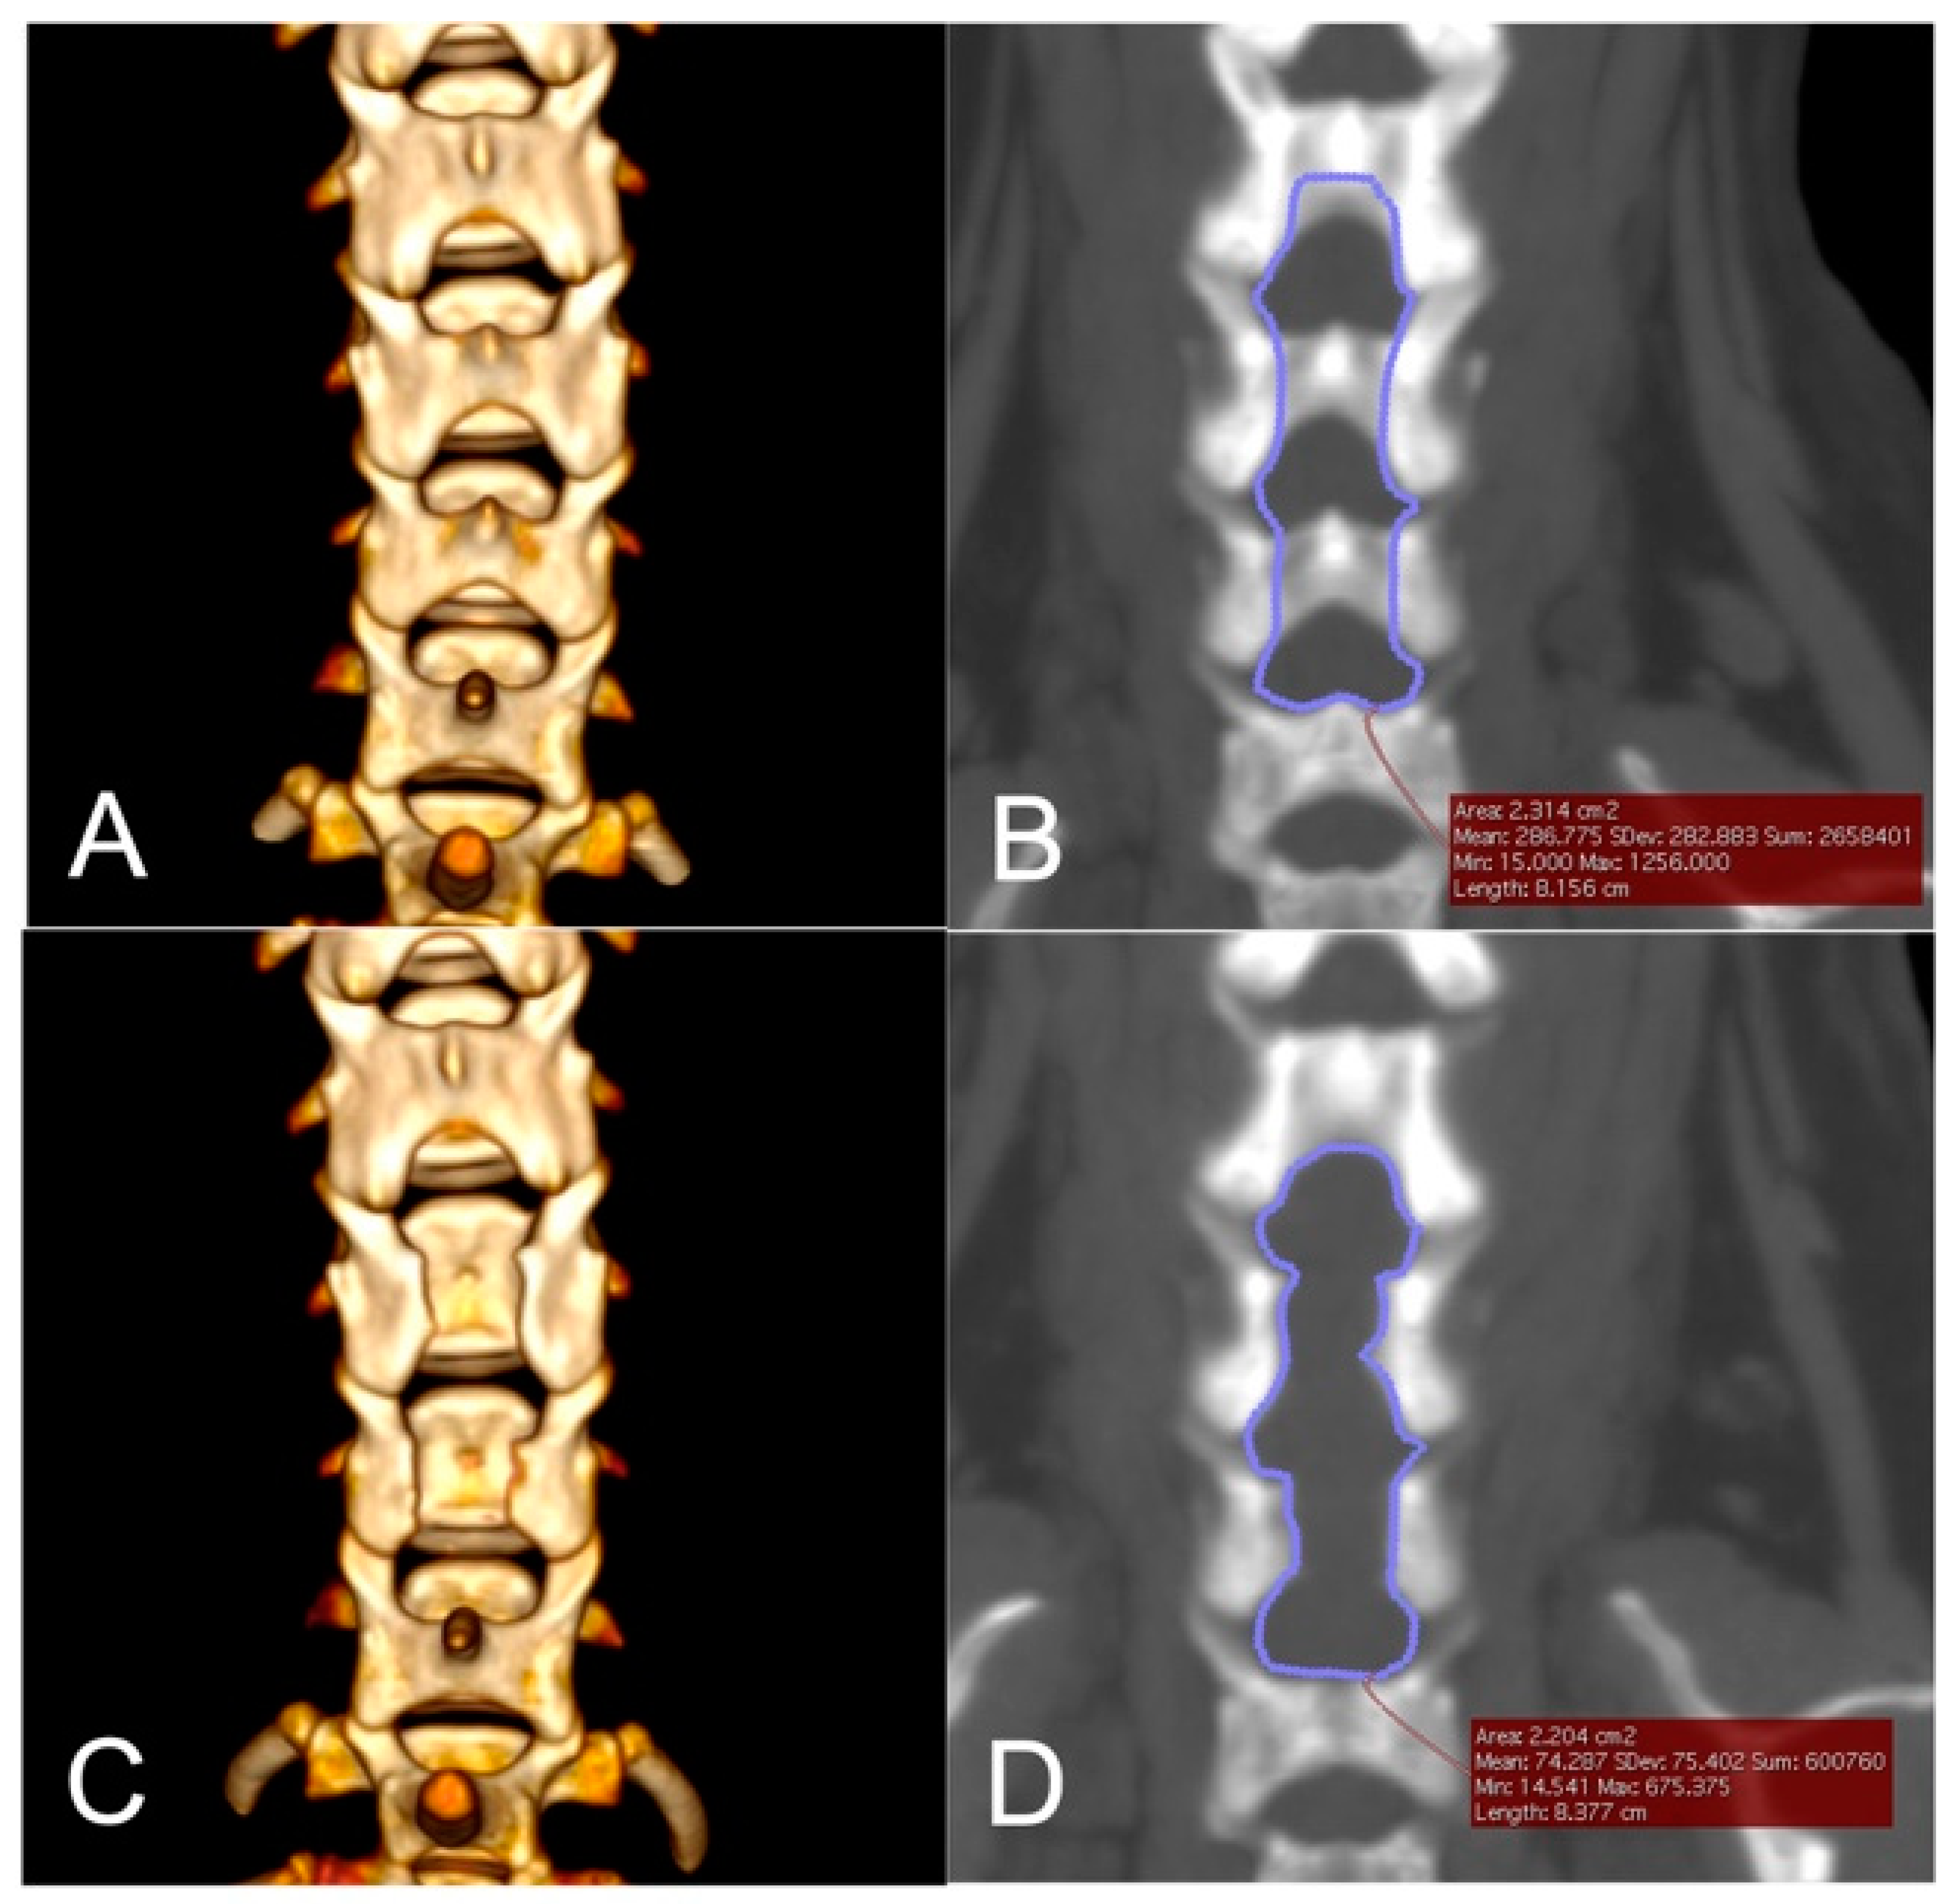

2.6. Imaging Analyses

3.4. Morphometric Analyses

| 2 | C4, C5, C6 | 125 | 15 × 40 | 26.5 | 2.314 | 2.204 | 95.25 |

| 3 | C5, C6, C7 | 189 | 19 × 40 | 19.1 | 3.552 | 2.682 | 75.51 |